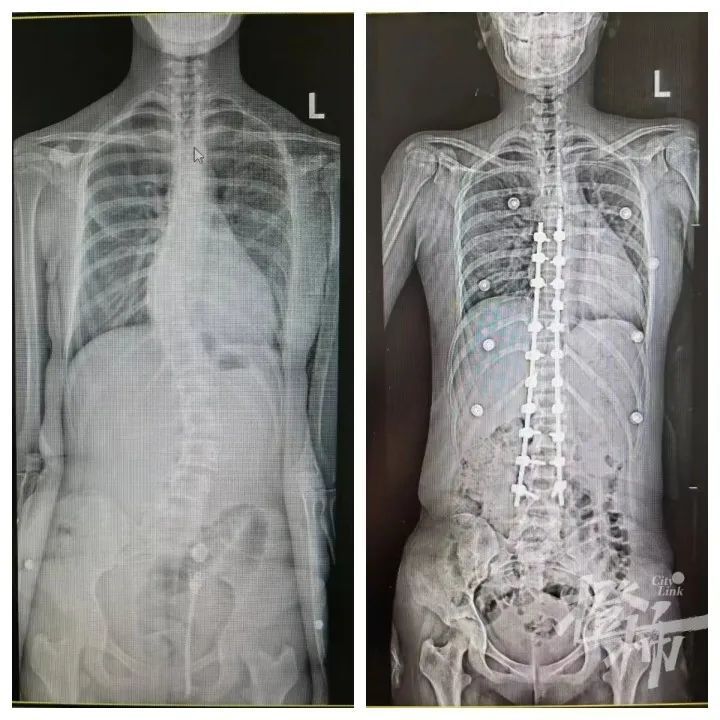

陈主任表示,马凡综合征患儿骨骼发育异常,跟一般的青少年特发性脊柱侧弯以及先天性脊柱畸形又有所不同,给矫正手术增加了一定难度,但好在最后可可的手术结果很不错,达到了预期效果。

可可手术前后的对比图 医院供图